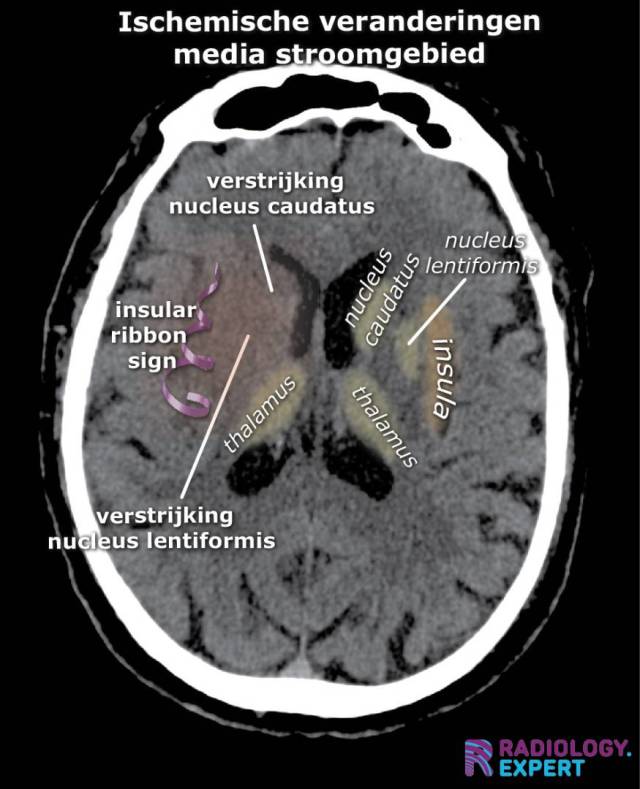

ischemische veranderingen op CT bij media infarct. Insular ribbon sign. Verstrijking basale kernen ischemische veranderingen op CT bij media infarct. Insular ribbon sign. Verstrijking basale kernen

Klik op afbeelding om overlay te zien